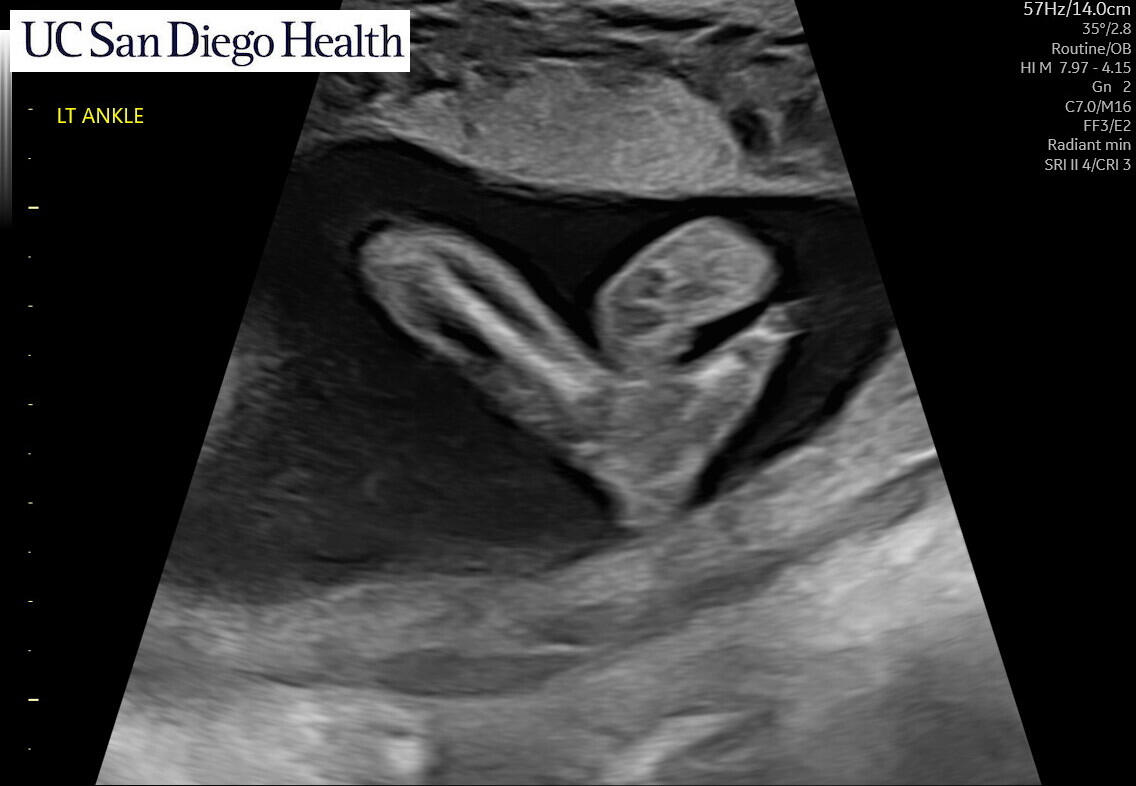

Coming March 2025!

We’re thrilled to be welcoming our baby boy in late March 2025! We’re planning a baby shower in January, we'll see you there!